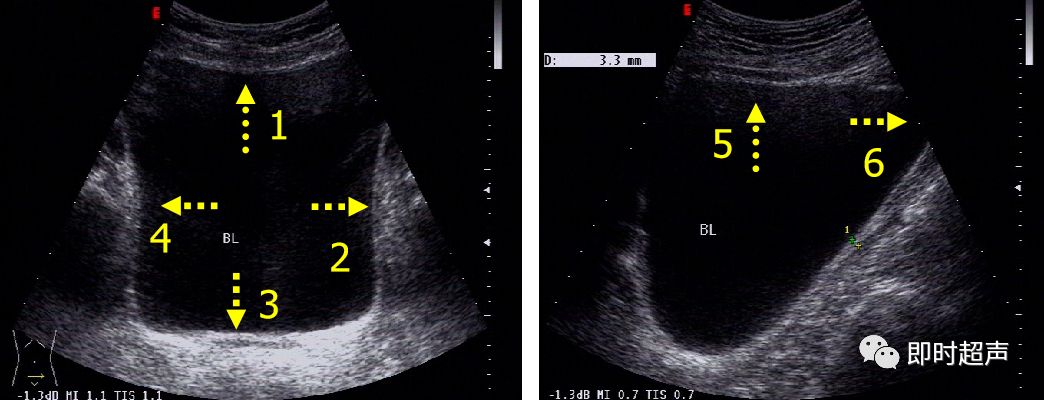

正常膀胱超声图像(经腹)

1.前壁 2.左侧壁 3.后壁 4.右侧壁 5.底部 6.顶部

膀胱三角区 (三角区位于膀胱后下部,为两侧输尿管开口及尿道内口所在区,是膀胱结核、膀胱肿瘤的好发部位 )

箭头所示为左右输尿管膀胱开口处